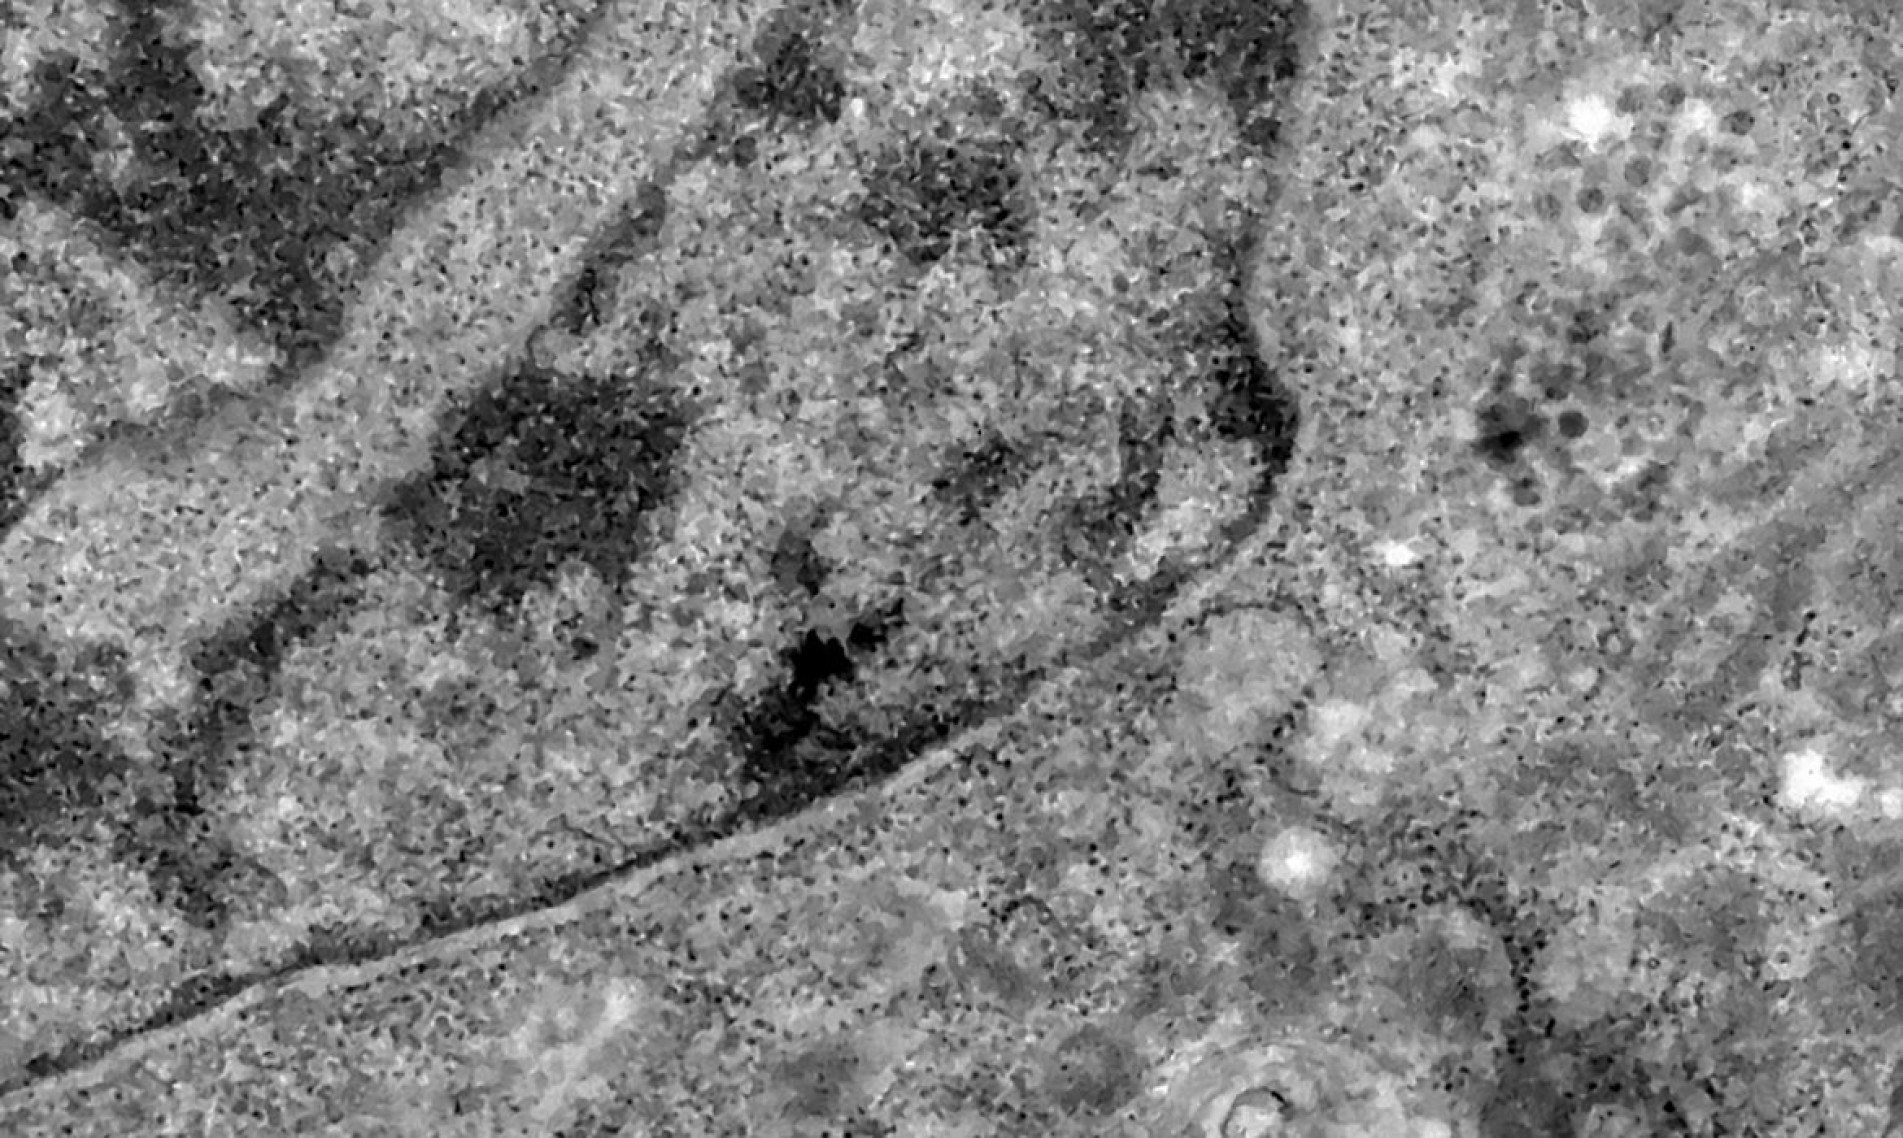

Nos casos analisados, constatou-se que a variante é portadora de dezenas de mutações genéticas que podem afetar os índices de contágio e de letalidade. A OMS, entretanto, afirmou que ainda não há estudos suficientes para afirmar as propriedades da Ômicron, mas que já existem esforços científicos acelerados para estudar as amostras. Um time de cientistas de universidades da África do Sul está decodificando o genoma da Ômicron, juntamente com dezenas de outras variantes do novo coronavírus.

Tulio de Oliveira, diretor do Centro para Respostas e Inovações Epidêmicas da universidade de KwaZulu-Natal, afirmou em coletiva de imprensa que a variante Ômicron possui "uma constelação incomum de mutações". A variante Delta, por exemplo, possuía duas mutações em relação à cepa original do novo coronavírus, enquanto a Ômicron possui cerca de 50 - 30 delas localizadas na proteína Spike, responsável por infectar células saudáveis, explicou o brasileiro.